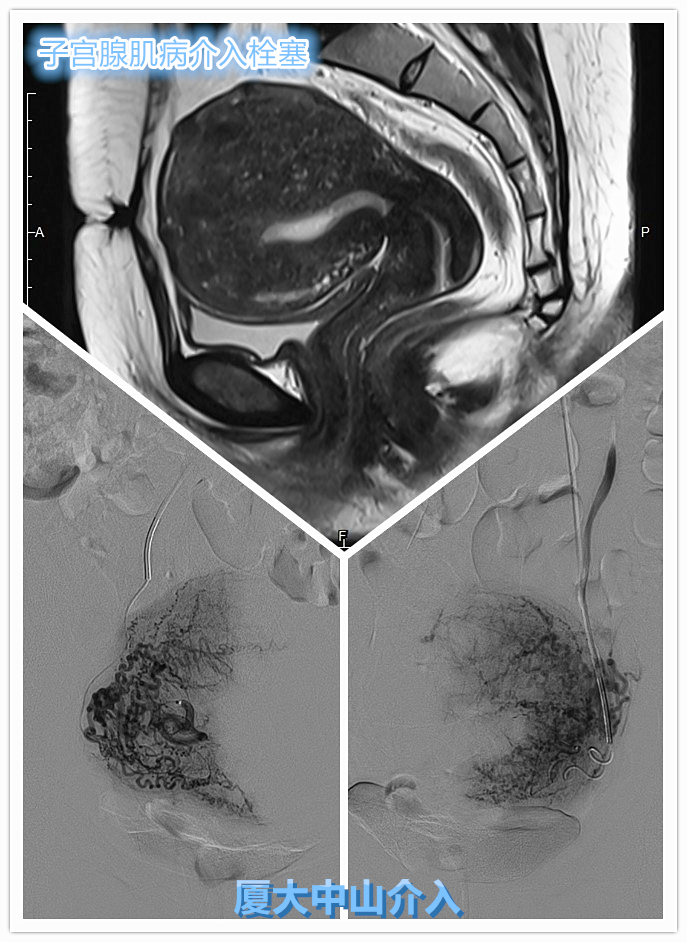

近期收治一位年轻子宫腺肌病患者,该患者已经生育3胎,在一胎后出现子宫腺肌病,痛经进行性加重。经咨询妇科建议可再生育治疗该病,但是在随后的二胎、三胎分娩后,痛经和月经量增多症状越发严重,患者甚至要求切除子宫以求彻底解决该病!

但因患者丈夫顾虑妻子尚较年轻,有较强保留子宫意愿,抱着一丝希望寻找其他替代治疗方法,争取保留子宫!所幸患者家属通过网络了解到,可以通过介入栓塞微创治疗子宫腺肌病,微创不开刀,可保留子宫!通过介入专病门诊就诊详询后,欣然接受介入微创治疗,术后恢复良好,相关症状亦得到明显缓解,生活质量明显改善!

目前临床上根治子宫腺肌病的唯一方法为子宫全切除术,而其他的治疗方法均存在或多或少的复发风险!而 子宫动脉栓塞(UAE) 因具备微创不开刀,完整保留子宫,术后恢复快,临床有效率高(80~90%)等优势,已经被国内外诊疗指南广泛推荐。 子宫腺肌症与介入栓塞的那些事

子宫动脉栓塞术示意图